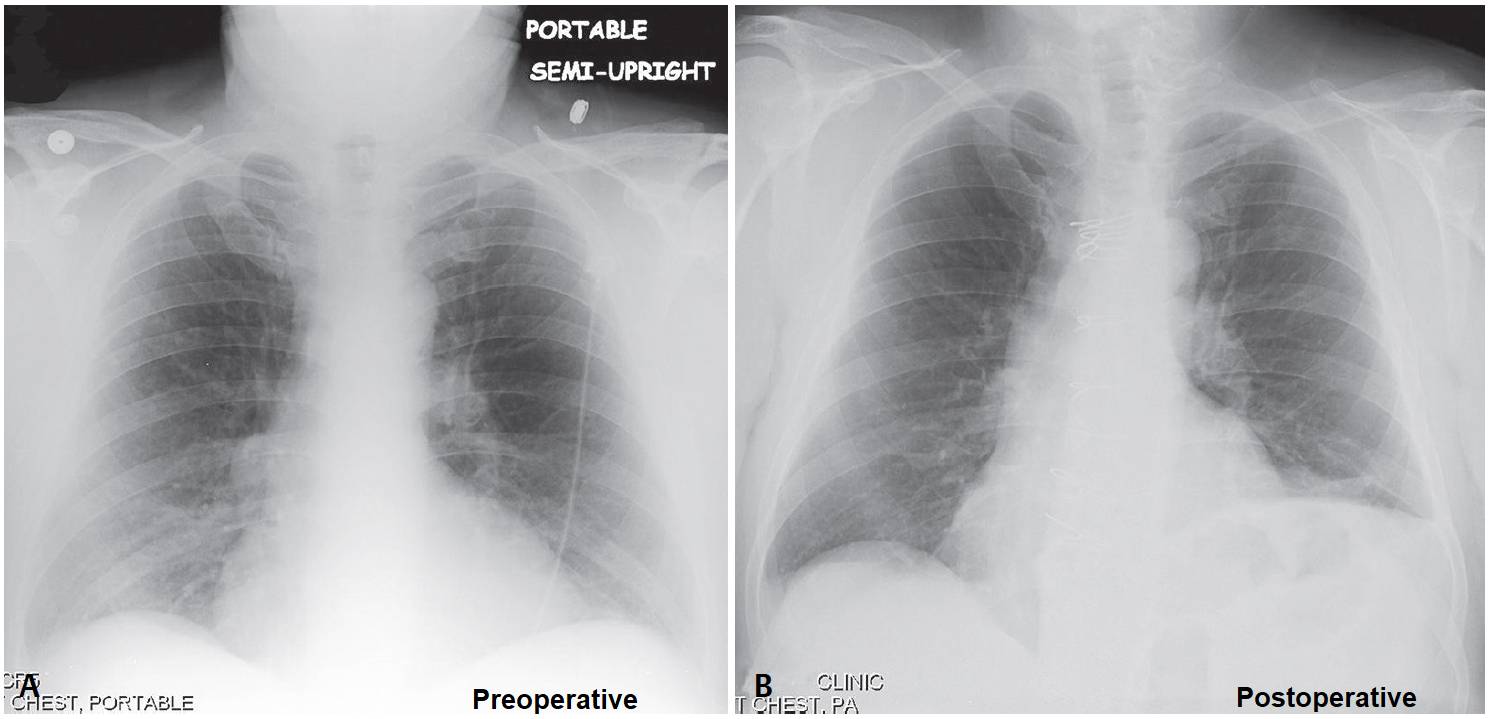

Dyspnea and Orthopnea after CABG Post category:Spot Diagnosis Post published:June 22, 2023 Share on Facebook Share on X (Twitter) Share on Pinterest Share on Email Share on Reddit Dyspnea and Orthopnea after CABG 45-year-old man 6-weeks status post CABG with complaints of increasing dyspnea on exertion and orthopnea who cannot tolerate lying flat and must sleep with his head elevated on 4–5 pillows. What’s the diagnosis ? FULL CASE AND ANSWER Share on Facebook Share on X (Twitter) Share on Pinterest Share on Email Share on Reddit Read more articles Previous PostReversible Facial Congestion After Elevation of Both Arms Next PostBluish Discoloration of Sclerae You Might Also Like Pretibial Hyperkeratosis, Fissuring, and Verrucous Nodules August 1, 2021 Patient with Bilateral Tender Fluctuant Masses Over Each Elbow November 19, 2021 Woman with Recurrent Right-Sided Chest Pain Synchronously with her Menses November 8, 2021